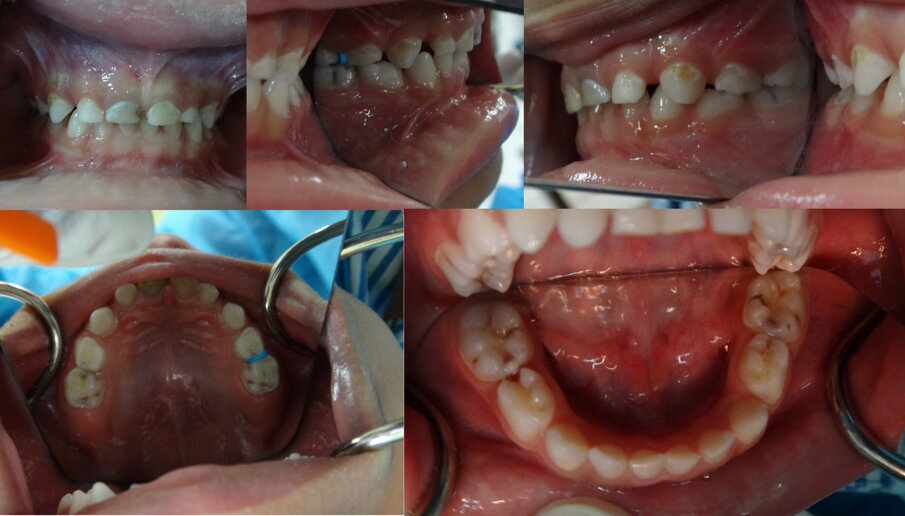

A fit and healthy three year old boy (MF) attended with his father to the Department of Paediatric Dentistry at Hamdan Bin Mohammed College of Dental Medicine (HBMCDM) in Dubai Healthcare City, Dubai (UAE). The father was concerned about ‘holes in his son’s teeth’. The father reported that MF suffered no pain whatsoever. After clinical and radiographic examination, MF was found to have multiple asymptomatic carious primary molar and incisor teeth fitting with the diagnosis of Severe Early Childhood Caries (S-ECC). Interestingly, MF’s eight carious primary molars (55, 54, 64, 65, 75, 74, 84 & 85) were free from symptoms of pain, and clinical and radiographic signs of pulpal pathosis. See Figures 1 (a, b, c, d & e) for clinical features, and Figures 2 (a & b) for radiographic findings.

Figures 1 (a, b, c, d & e) are showing typical dental caries in a 3 year old. He had no symptoms whatsoever. In Figures 1 b & d an orthodontic separator can be seen fitted distally to 64.

Figures 2 (a & b): Bitewing radiographs showing caries on all Ds and Es. There were clear bands of dentine between the carious lesions and the pulp. There were no radiographic signs of interradicular pathology. Although the furcation areas of upper Es were not visible, no further xrays were justified as the upper Es had shallow radiographic lesions.